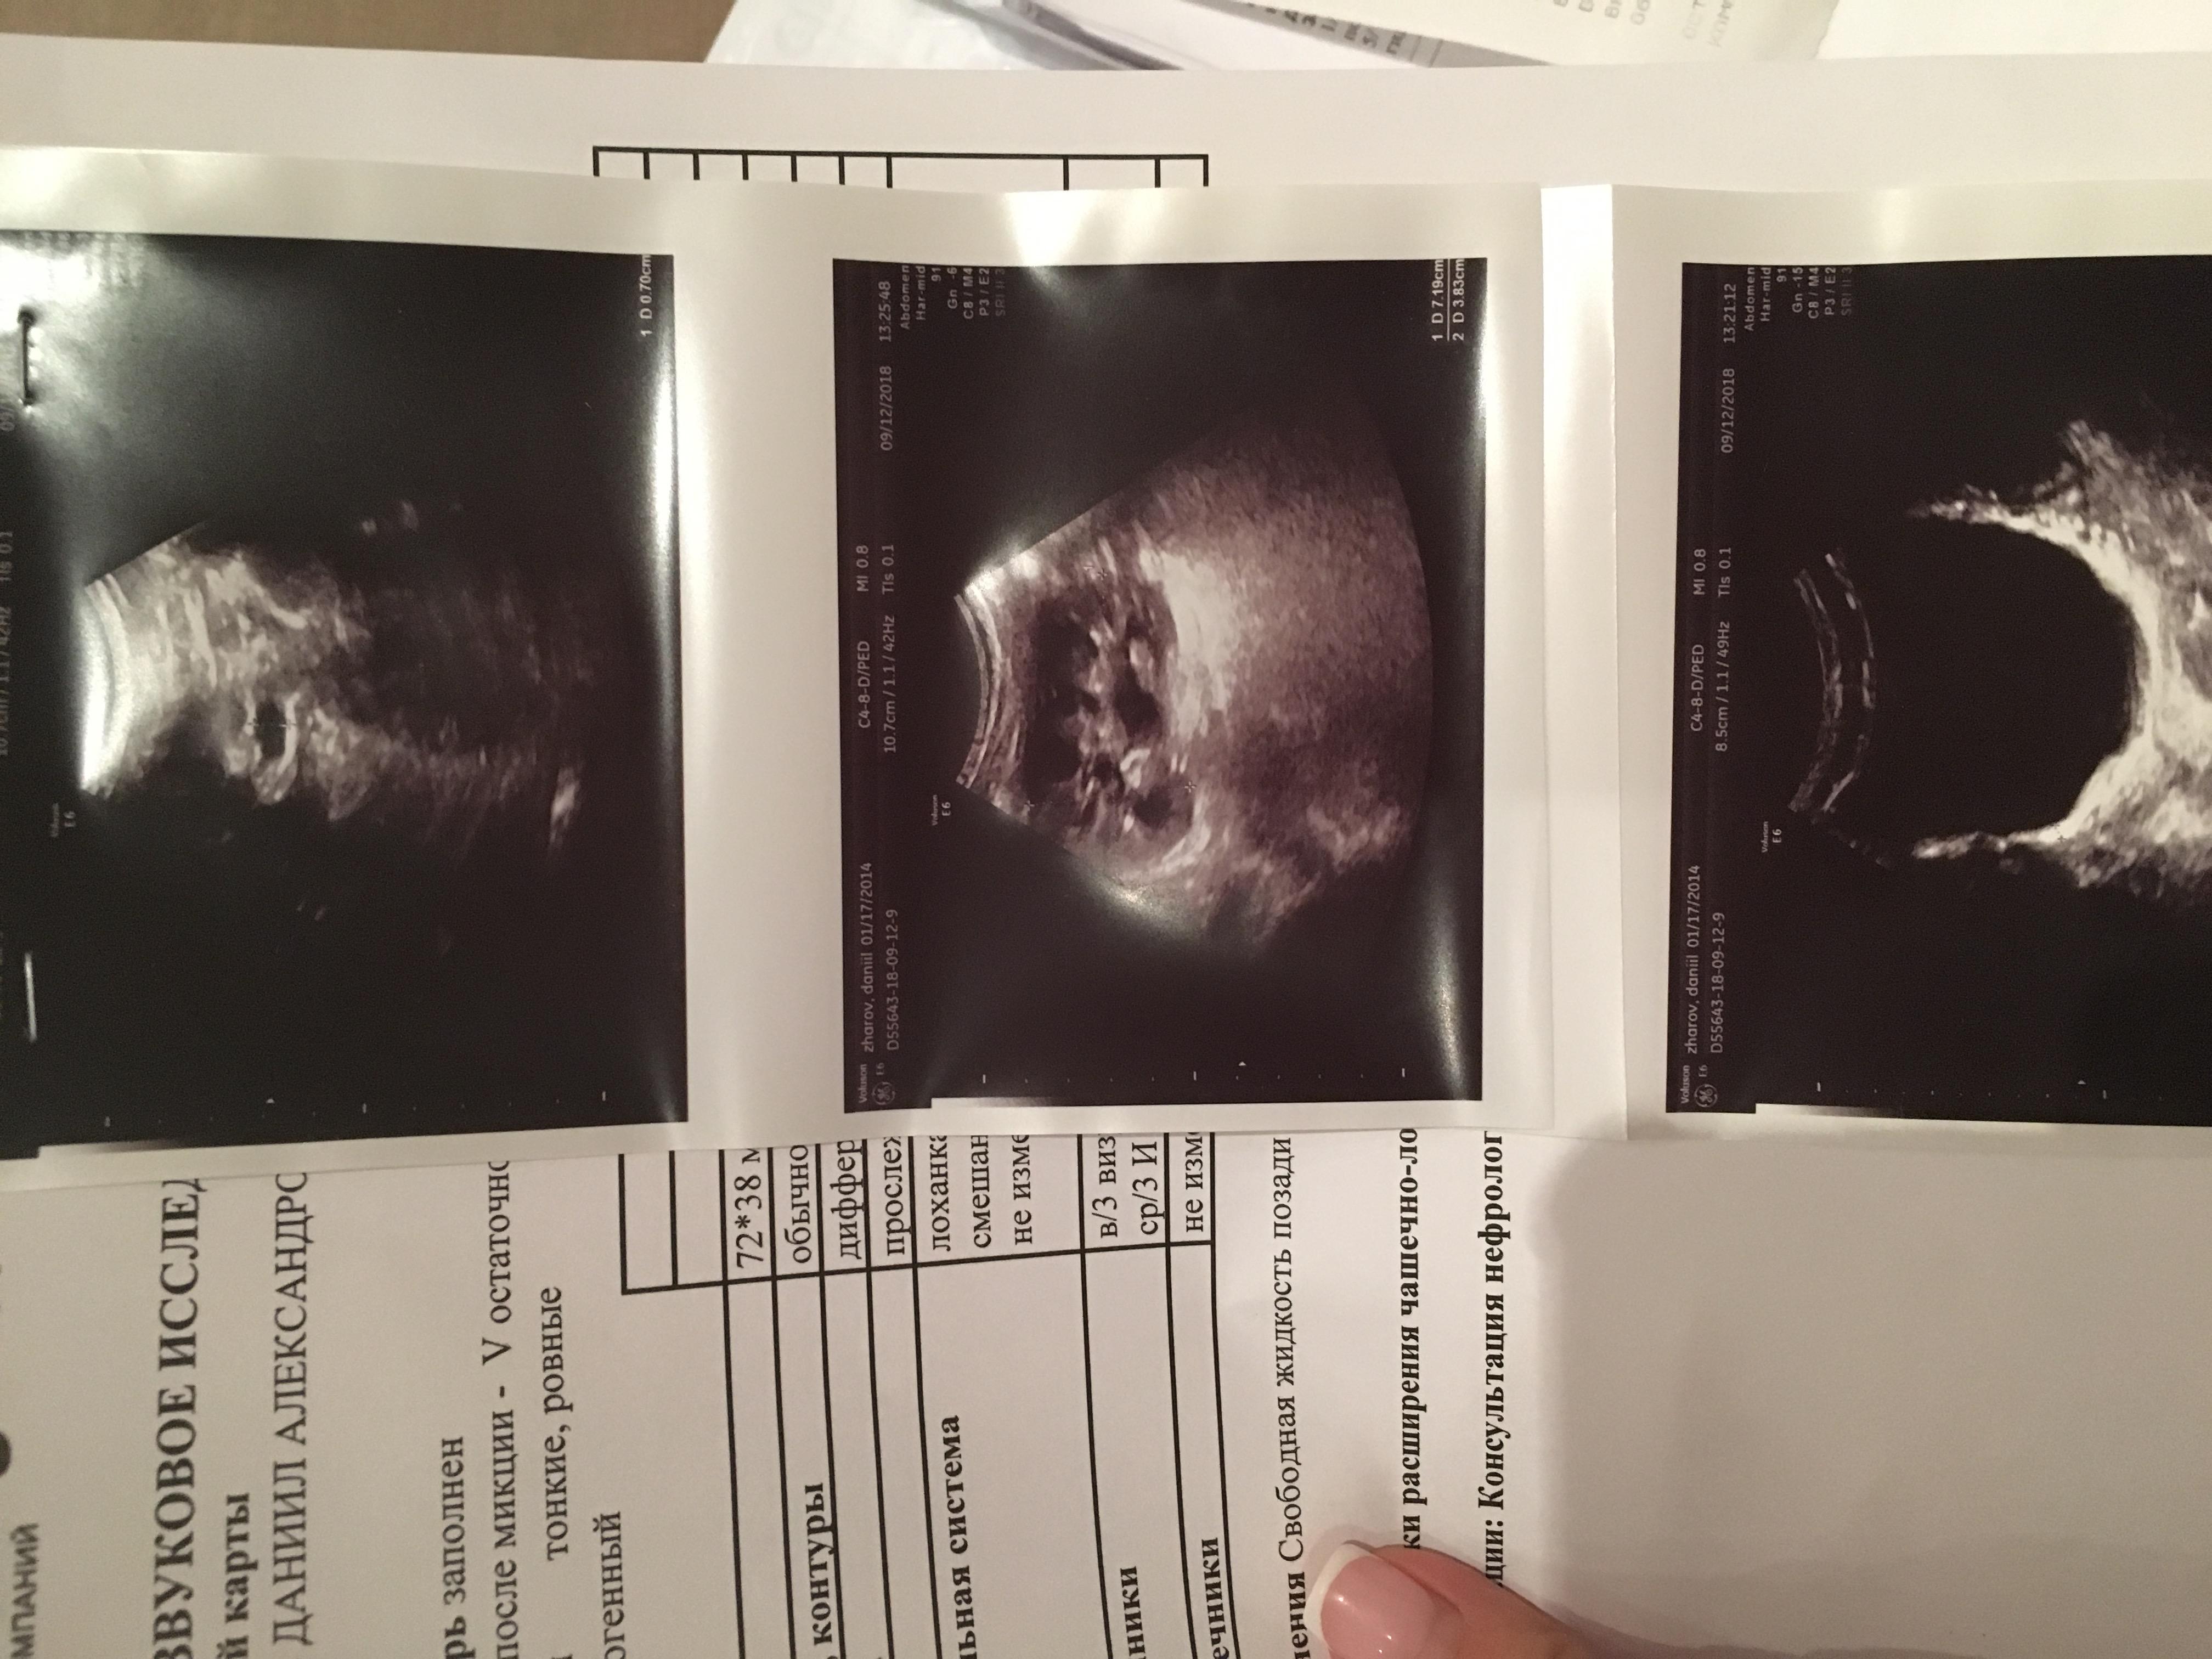

при рождении и в 3 месяца почки были без изменений.В 1 год 1 месяц после ОРВИ у ребенка появился запах ацетона в моче, в бак.посебе протеус мирабилюс 10*6 степени, лейкоциты в оам-30,УЗИ-левая лоханка 5 мм,все остальные показатели в норме,пропили антибиотик зиннат, далее фурагин,канефрон,согласно рекомендациям нефролога. Контроль УЗИ после лечения-норма,оам-идеальный.В 2 года узи -левая лоханка 8 мм,правая 8, чашечки не уанличены,остальные показатели в норме.В 3 года узи: лоханки левая 5 мм,правая 4 мм,все остальные показатели в норме,оам-норма.В 3.10 мес(ноябрь 17г)ребенку поставлен диагноз-нейрогенный мочевой пузырь(узи,урофлоуметрия),оксалурия( в Ноябре 17г. (до этого в октябре 17г. перенес орви с темп.40),Темп 38.5 без признаков орви,мутная моча,частое мочеиспускание малыми порциями,осадок в горшке кирпичного цвета, по оам все показатель в норме, кроме солей(ураты,оксалаты)в большом кол-е). Согласно результатам узи левая лоханка 22 мм,остальные показатели в норме.Лечились у нефролога,поэтапно принимали препараты для почек(фурагин,канефрон,трава пол-пола,донат магния,мин.вода фьюджи,витамин в6,веторон), для кишечника(эубикор крошка,кидз саше,лактофильтрум), диета 5 и питьевой режим 1.6 л в день,сахар по глюкометру 4.7.Вели дневник Мочеиспусканий в теч.4 дней,в среднем обьем выпитой жидкости составлял 1,5, обьем вырущенной 1.4.,мочился больше 12 раз в день.Мочеиспускание без затруднений. После лечения сделали узи,члс была в преднлах нормы, но диагностирован нейрогенный мочевой пузырь( пописал 250 мл, осталось 10 мл).анализы мочи -не придраться. Придерживаемся диеты 5 с февраля 18 г по сей день,выпиваем воды 1.6 л в день.22 августа прошли диспансеризацию и сделали для контроля узи почек/ доплер на высокочувствительном аппарате, результаты обследования меня мягко сказать огорошили- по узи чашечки расширены слева 5 мм(прежде расширений чашечек никогда не диагностировалось),лоханки слева 11 мм ,плюс в почках обнаружен песок, остальные показатели в норме,доплер-сосуды в норме.ОАМ-норма.Получается во время приема мочегонных препаратов, лоханки в норме(за исключением нейрогенного мочевого пузыря он имеет место быть),как только перестаем лечиться образуются соли .. хотя сидим на диете и пьем много воды. 4 сентября в ницрр сделали динамическую сцинтиграфию с микционной пробой, по результатам обследования функция почек не нарушена,но,слевой стороны обнаружен незначительный лоханочно-чашечный рефлюкс( результаты обследования, узи и пр.прилагаю).Какие наши дальнейшие действия? Складывается такое впечатление,что все это время мы бечили следствие заболевания,а не саму причину.. Заранее благодарна за ответ!